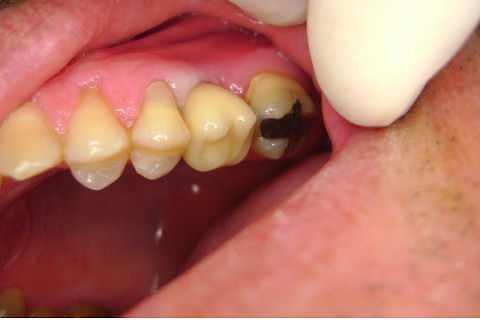

Instalação de um implante em região do 26. Utilizamos um implante cone morse Alvim Neodent 4.3 X 11,5. Foi uma cirurgia muito rápída e minimamente traumática, sem retalho e sutura.

Fotos do caso